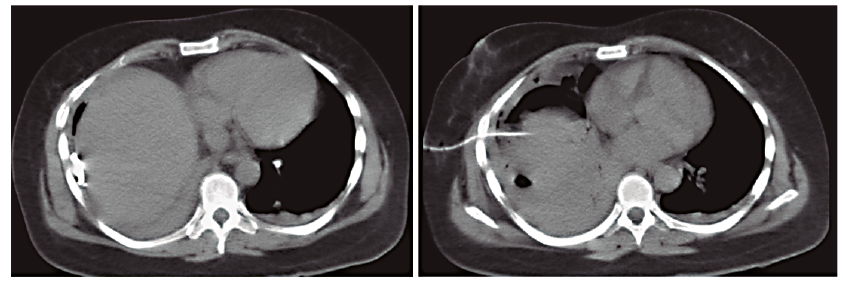

Con este hallazgo se decidió realizar el drenaje percutáneo de dicha colección bajo guía ecográfica, con la colocación de un catéter multipropósito de 12 Fr, lográndose evacuar 400 ml de líquido hematopurulento, cuyo cultivo fue positivo para Escherichia coli sensible. A las 24 horas, debido a que la paciente continuaba con sintomatología respiratoria, se realizó una nueva TC que evidenció una disminución marcada del componente líquido de la colección, persistencia de la imagen con contenido aéreo en contacto con la cúpula diafragmática y el agregado de un derrame pleural homolateral. Se decidió realizar el drenaje percutáneo guiado por tomografía de la colección residual subfrénica y la punción del derrame pleural, cuyo resultado fue interpretado como un empiema debido al examen físico-químico (aspecto turbio, ácido láctico 20 mg%, LDH 4.431 UI/l, glucosa 11 mg% y cultivo positivo para Escherichia coli sensible (Figuras 4 y 5). El empiema pleural fue manejado inicialmente con un tubo de avenamiento derecho, y posteriormente, dado que no se logró el drenaje completo y se observó un peel pleural, se realizó una decorticación por toracotomía con resolución completa de la patología pleural. La paciente evolucionó favorablemente con seguimiento ambulatorio. El hematoma se resolvió completamente y el drenaje se retiró a los 46 días (Figura 6).